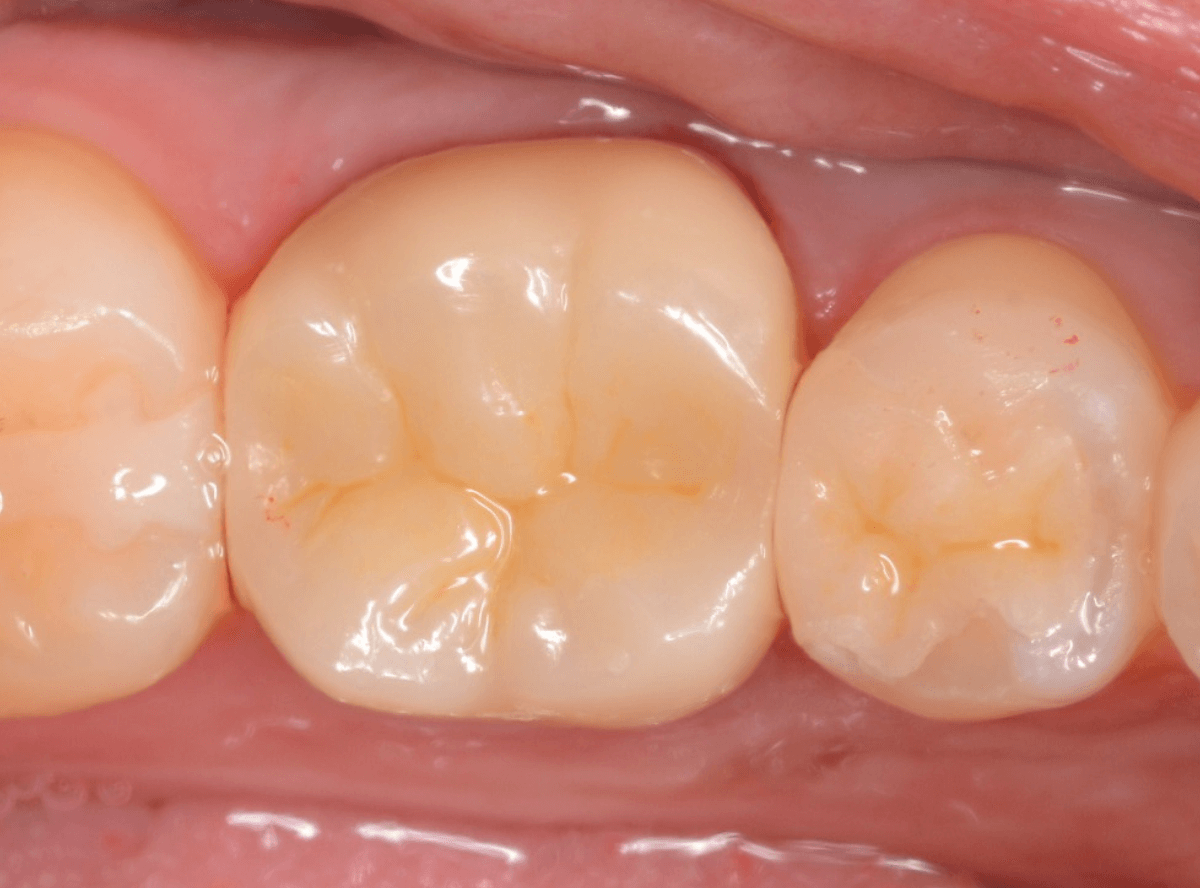

set後の写真です。

患者さんにも満足していただける仕上がりになりました。

治療前後の比較写真になります。